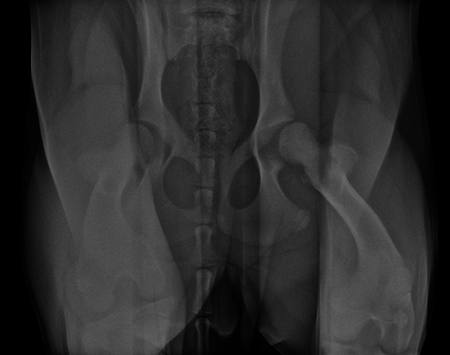

A 4-month-old female boxer puppy weighing 15.0 kg presented with bilateral hind limb weakness and reluctance to walk. Physical examination revealed bilateral hip instability (positive Ortolani sign) and severe pain on full extension of the hips. The neurological exam was normal. The radiographs revealed bilateral hip subluxation and a distraction index of 0.65 of the right hip and 0.6 of the left hip (Fig 7). Very mild osteoarthritis was seen and femoral head coverage by the dorsal acetabular rim was good (Fig 8). Angles of subluxation (10° R and 20° L) and reduction (30° R and 40° L) of the hips were measured under anesthesia.

A diagnosis of juvenile hip dysplasia was made. Both hips were considered as candidate for double pelvic osteotomy (DPO). Considering the difficulty to limit the activity of this active puppy, a simultaneous bilateral procedure was not performed. The left hip DPO was performed first, followed by the right hip 4 weeks later.